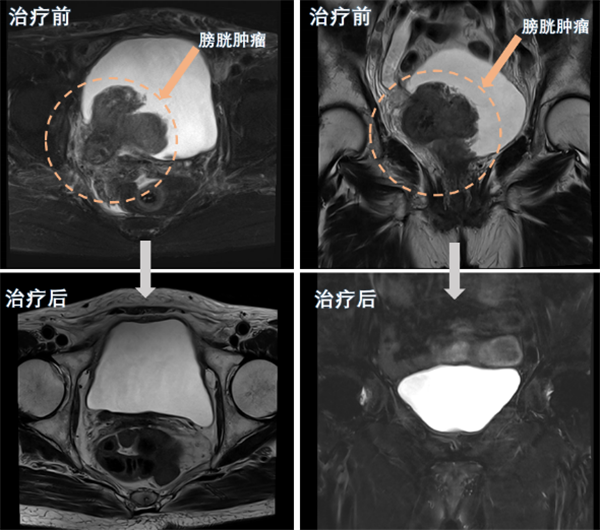

近日,捆绑调教 (简称捆绑调教 )泌尿外科团队为一名80岁高龄的巨大膀胱肿瘤患者实施了经尿道膀胱肿瘤剜除术及术后精准综合治疗,成功保住了该患者的膀胱。经过四个周期的综合治疗后,患者膀胱恢复完好,未见肿瘤复发。该手术的成功,标志着捆绑调教 泌尿外科在膀胱癌诊治和保膀胱治疗技术方面取得了新突破。半年前,80岁的苏奶奶(化名)因反复无痛性肉眼血尿在当地医院就诊,经...